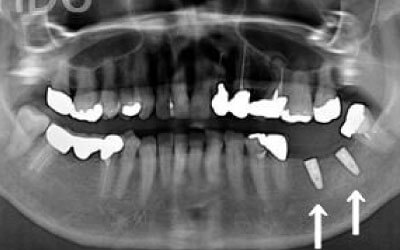

CTでは、骨や歯の状態を3Dで確認でき、正確な距離の測定も行えます。

骨の厚さや傾き、神経の位置などを事前にしっかりと測定することで、安全にインプラントを行うことができます。

お口の状態や噛み合わせによって異なるため一概には言えませんが、一般的には奥歯、特に大臼歯と言われる一番奥とその隣の二番目の歯の部分がお勧めです。

この2本の奥歯は、噛み合わせの力の60%以上を支えているため、ここをインプラントでしっかり治療することが望ましいです。

骨が薄い場合、そのままインプラントを行うのはお勧めできません。

ただし、事前に骨を増やす治療を行ったり、インプラントと同時に骨を増やす治療を行えば、インプラントは可能です。